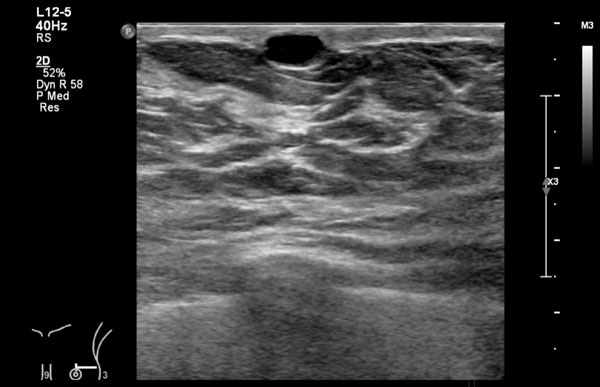

Đây là hình ảnh siêu âm bình thường của tuyến vú.

Lớp xám phía trên là da.

Tiếp theo là sự pha trộn giữa mô mỡ (tối hoặc giảm âm) và mô tuyến (xám sáng hoặc tăng âm).

Lớp có vân sọc phía sau mô vú là cơ ngực.

Phía sau hoặc sâu hơn so với xương sườn có một vùng đen hay bóng cản âm phía sau.

Phổi là lớp có thể quan sát sâu nhất.

Không khí trong phổi phản xạ hầu hết sóng âm, tạo ra một đường sáng hoặc tăng âm với bóng cản bẩn phía sau.